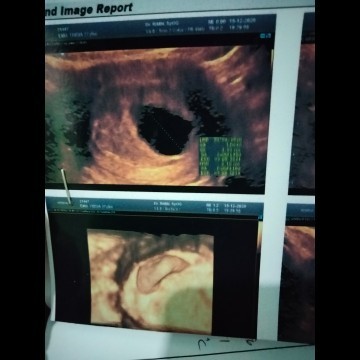

Abnormal pragnant

Assalamualaikum bunda..saya mau tanya kata dokter janin saya tidak berkembang diusia 8 minggu ,bunda" ada yg pernah ngalamin seperti itu?mohon infonya nya bunda terima kasih π